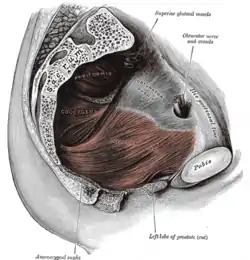

Anatomy of the anus and rectum Left levator ani from within

Left levator ani from within The interior of the anal canal and lower part of the rectum